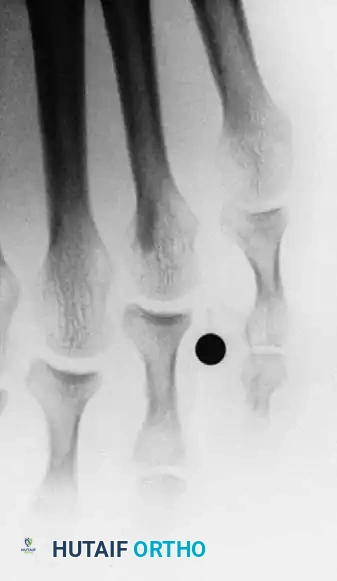

Fig. 80-23 A, Fourth web space interdigital corn. B, Corresponding radiograph with marker overlying corn. Note two-boned fi fth toe and abnormally short fi fth metatarsal. C, Oblique view showing apposition of base of fourth proximal phalanx and head of fi fth proximal phalanx.